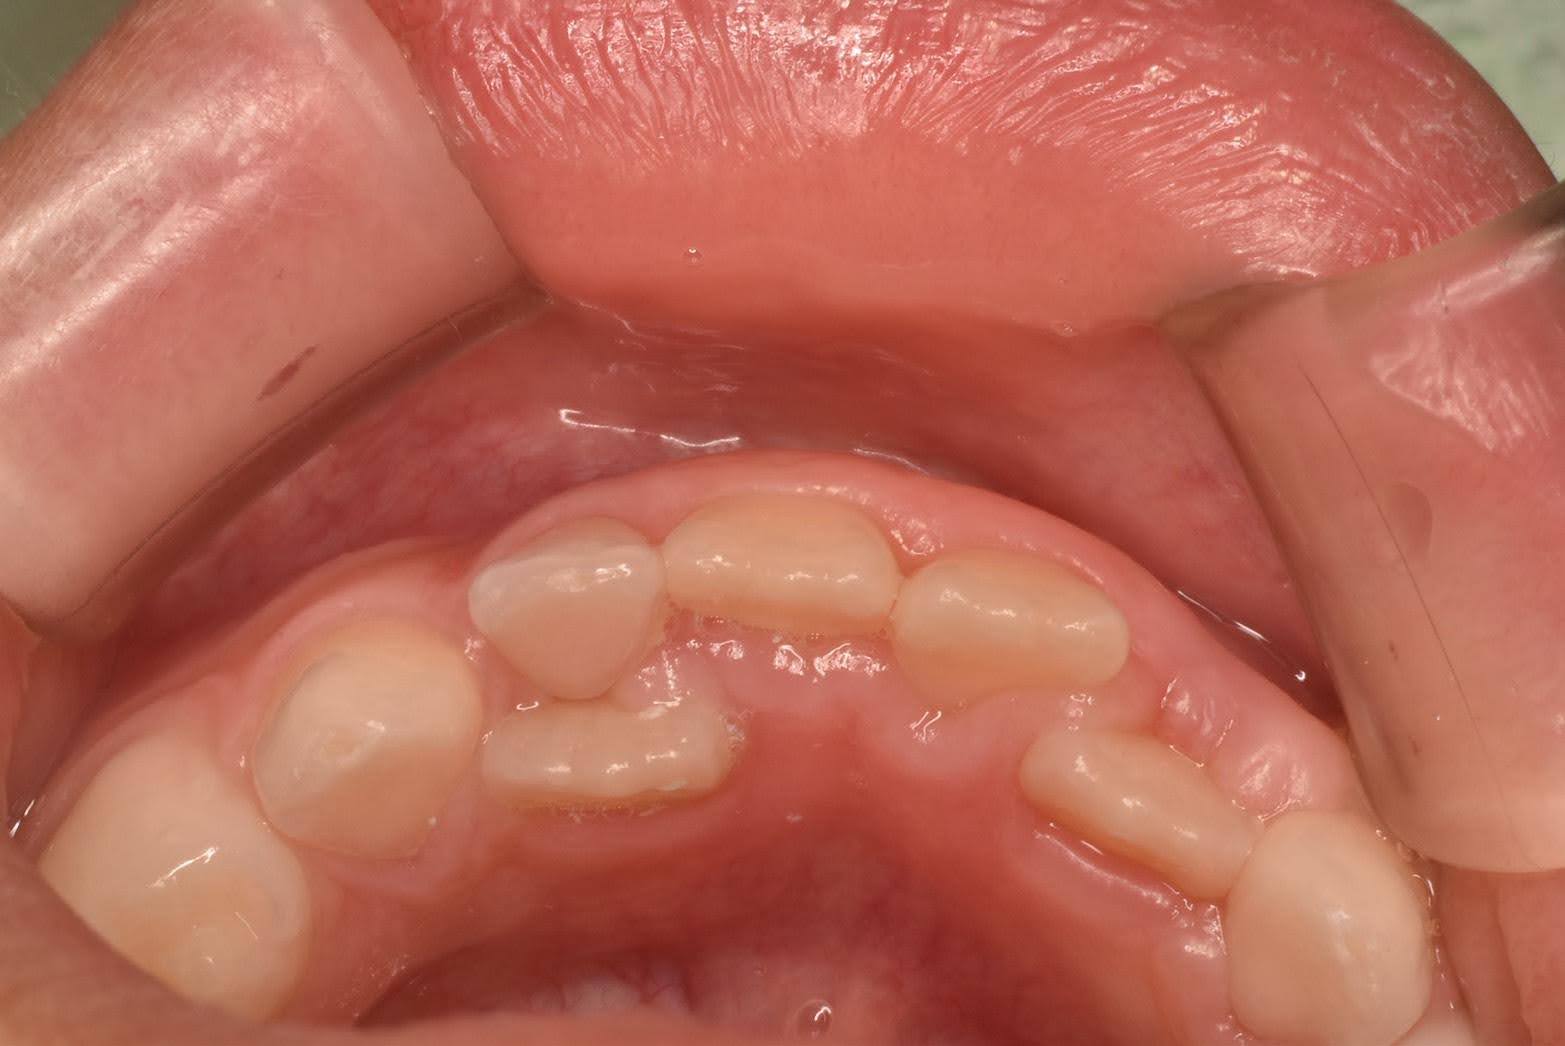

代表的なのは、上のような、下の顎の前歯が乳歯の後ろ側から萌出(ほうしゅつ)してくるケースですね。「二重に歯が生えてきた!」と驚かれることもありますが、実は珍しいことではありません。